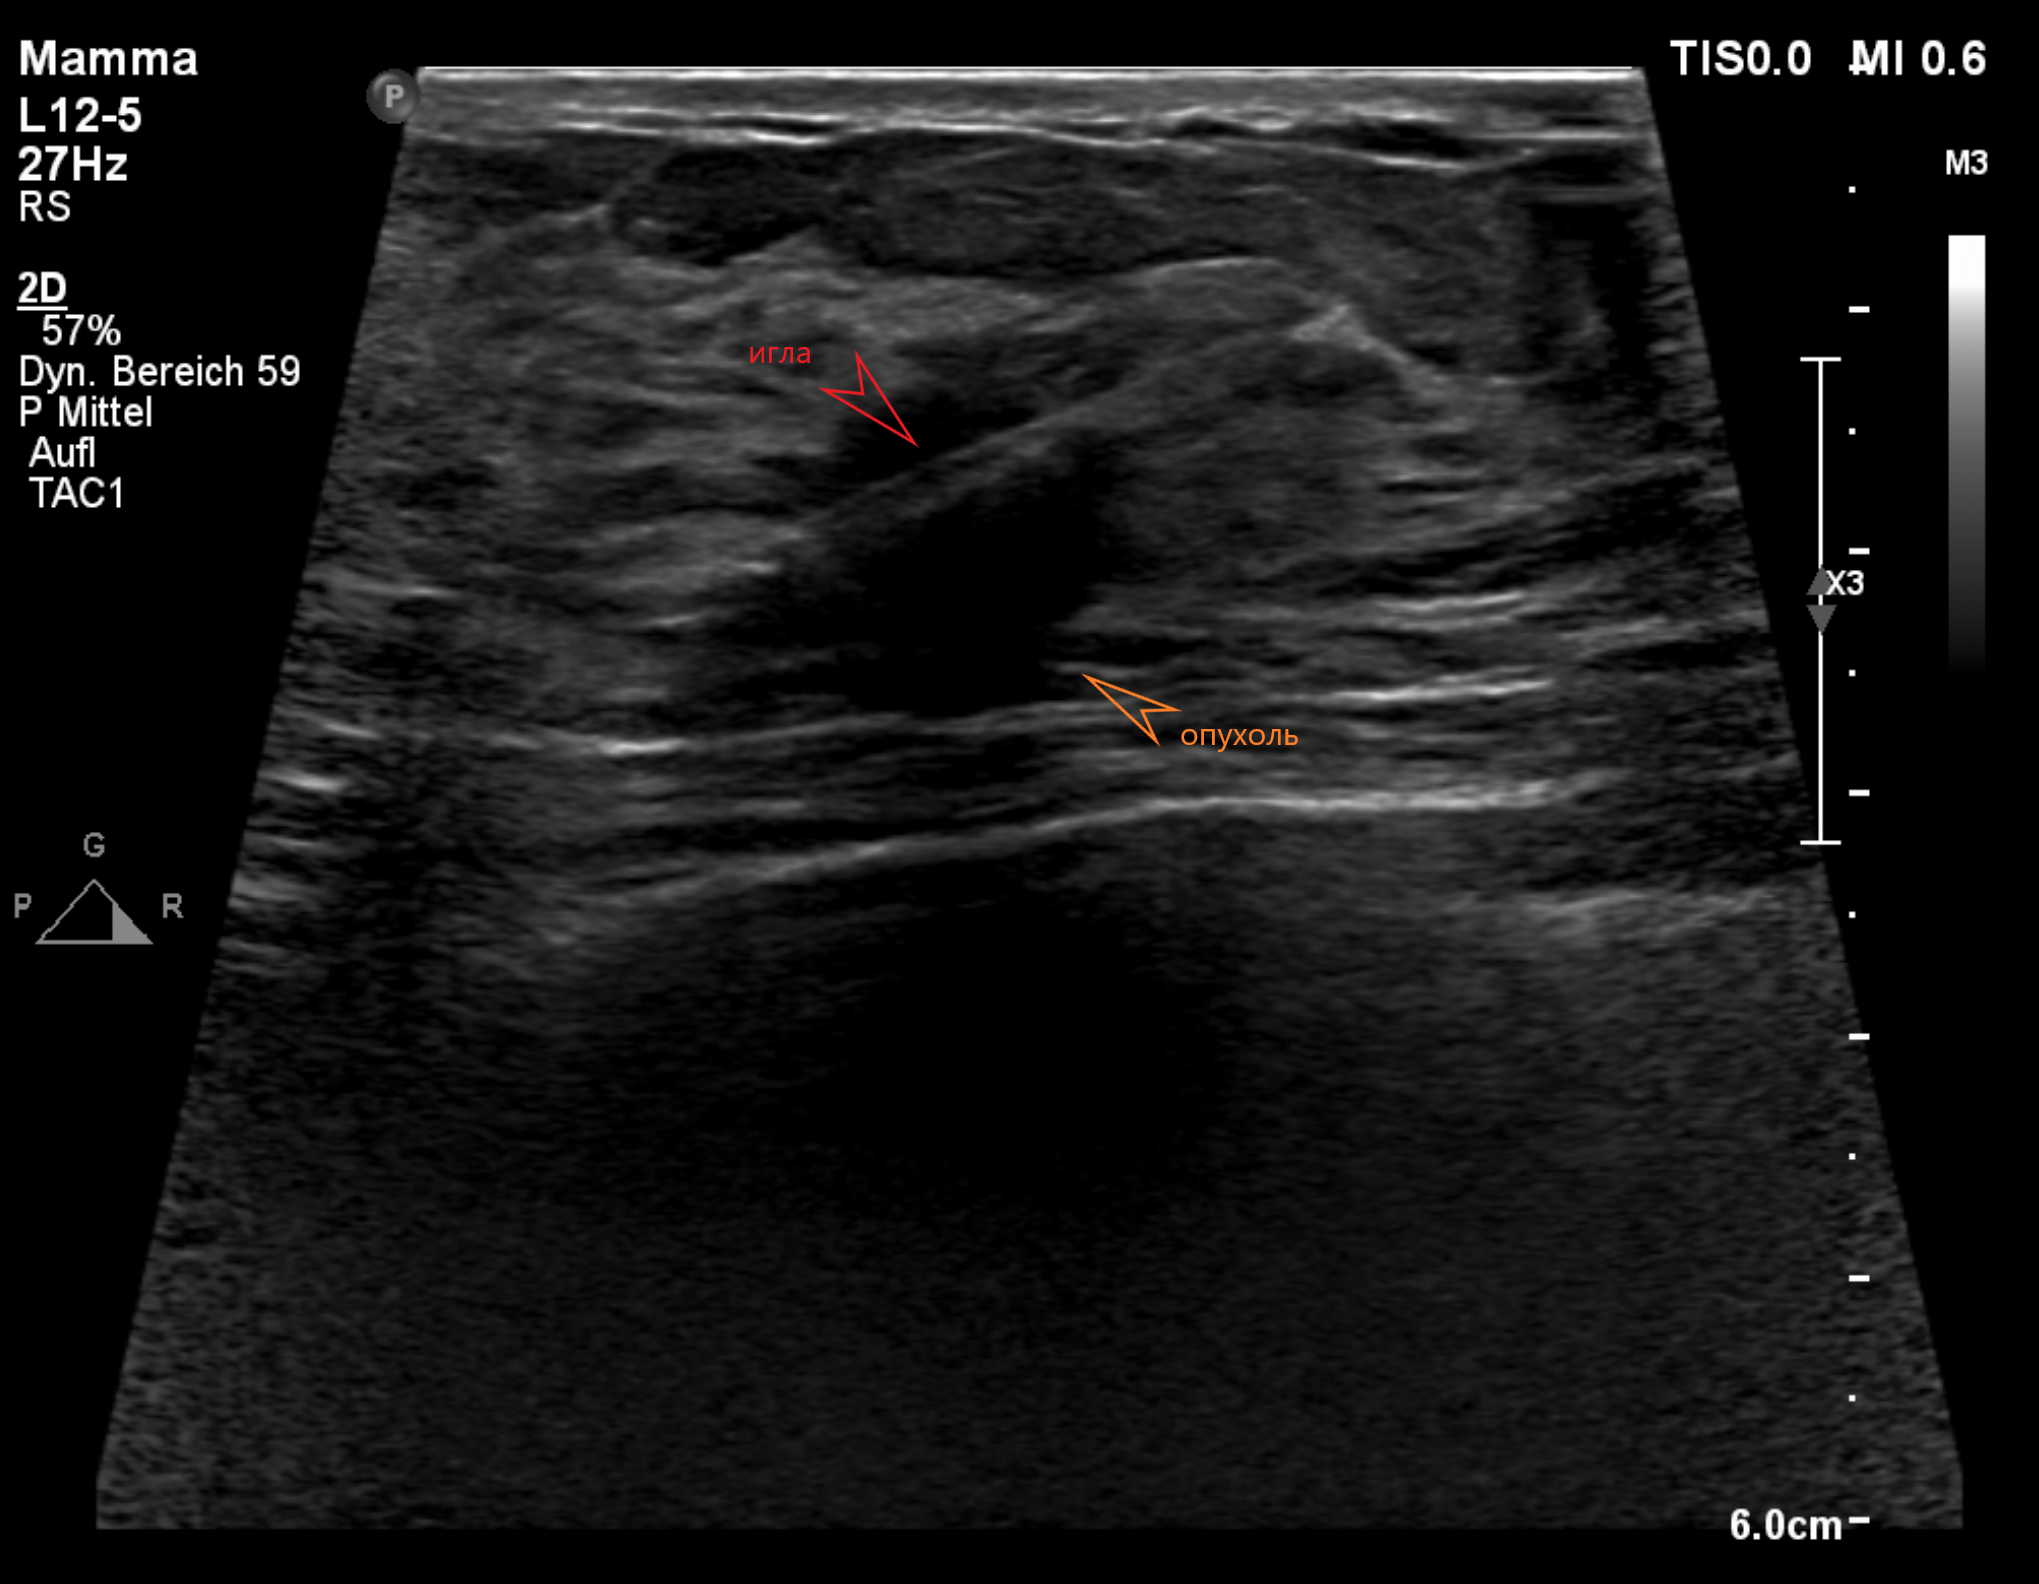

Сразу после маммографии провели ультразвуковое обследование, где очаг хорошо определялся как сильно гипоэхогенная область (мало отражающая УЗ лучи) с нечёткими контурами и ориентировкой перпендикулярно плоскости кожи:

Все вышеуказанные признаки характерны для рака молочной железы, что подтвердила последующая биопсия (проведена тоже мной, под контролем УЗИ):